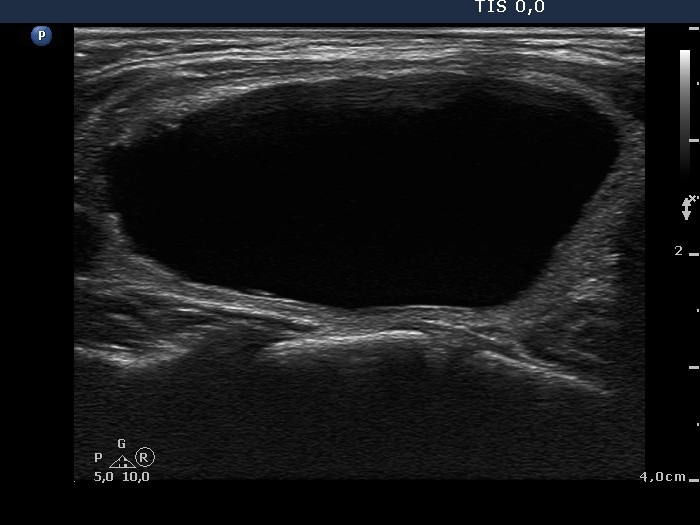

Ethanol sclerotherapy: other examples - Case 3: treatment of a gelatinous thyroid cyst

Three months prior to therapy (ultrasonographic picture 2)

Right lobe, longitudinal scan.